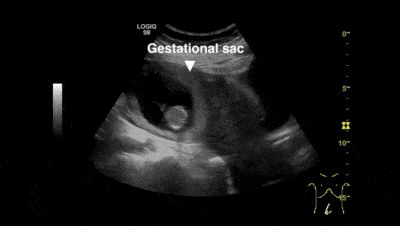

原标题:输卵管间质部妊娠(急腹症)当年普外轮转时,科里有位高手,看到新收住院的一位面色苍白、弓腰捂着肚子的年轻女患,他随即对管床大夫说,这个阑尾炎可别是宫外孕……今天这个病例使我想起了过往。对于全科医生,超声就相当于未来的听诊器,是最实用的诊断手段,可惜以前都是只看回报,典型的声学检查的影像,没机会...